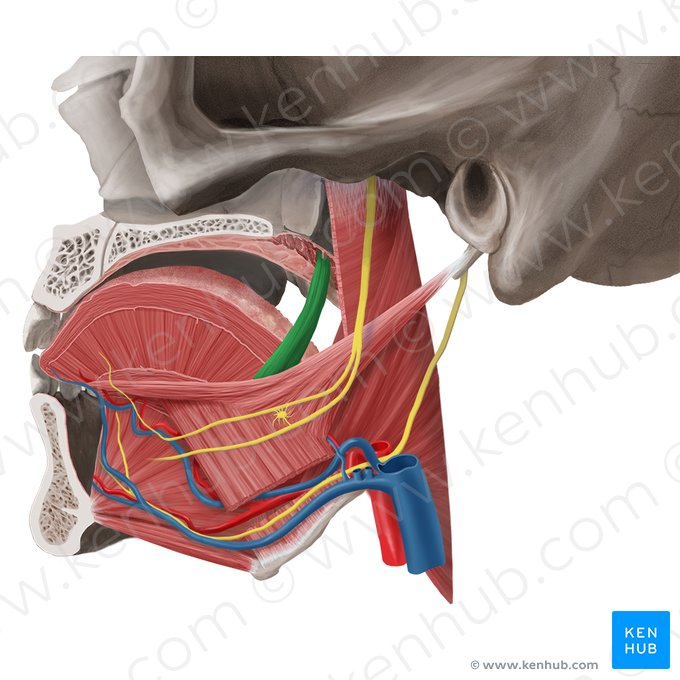

Genioglossus

Hyoglossus

Palatoglossus

Styloglossus

Nasopharynx

yellow highlight

Oropharynx

green highlight

Laryngopharynx

blue highlight